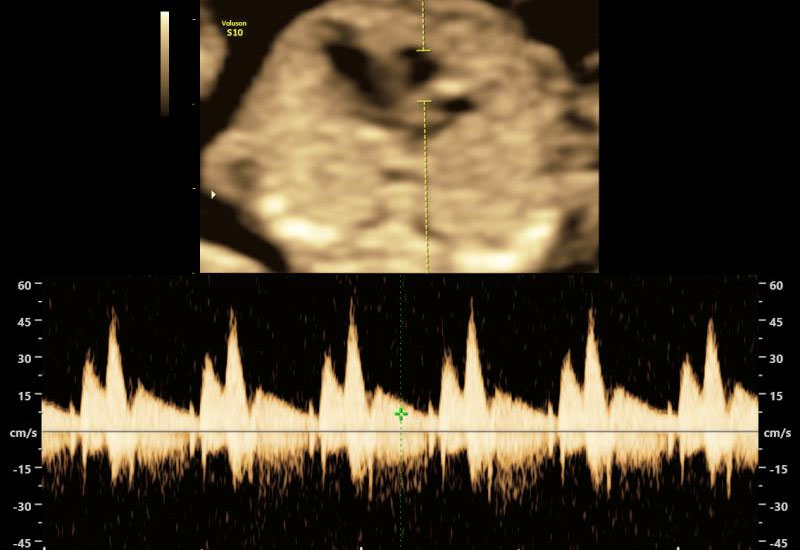

- Fetal heart rate

The NT measurement is combined with:

- Doppler studies (as indicated)